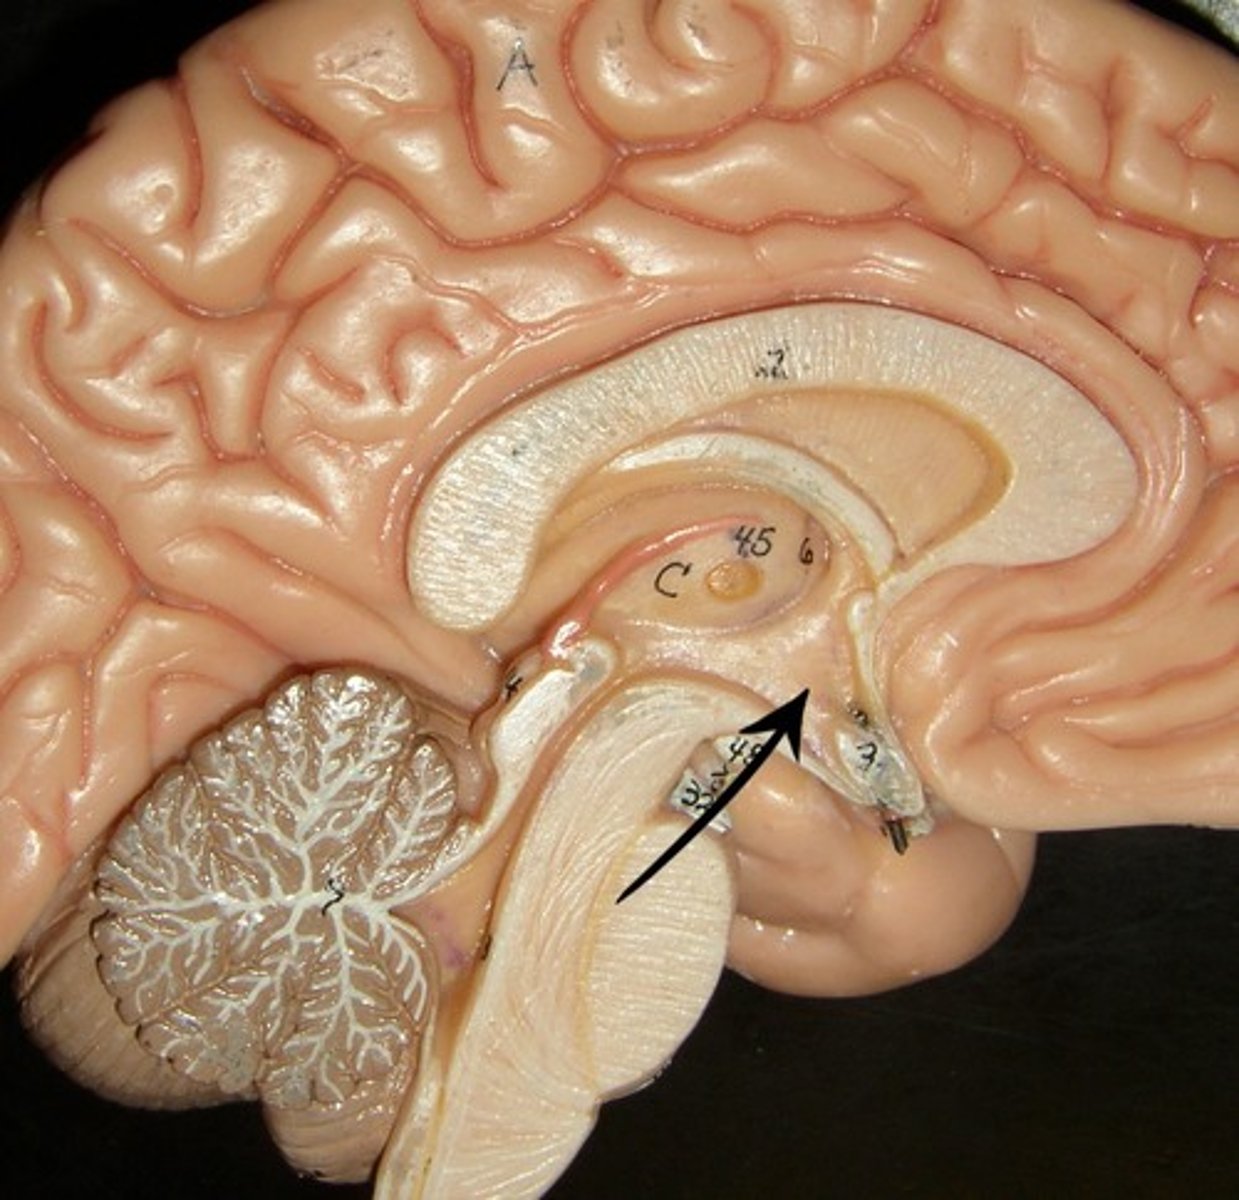

corpus callosum

lateral ventricles

3rd ventricle

4th ventricle

cerebellum

thalamus

hypothalamus

midbrain

pons

medulla oblongata

cerebral aqueduct